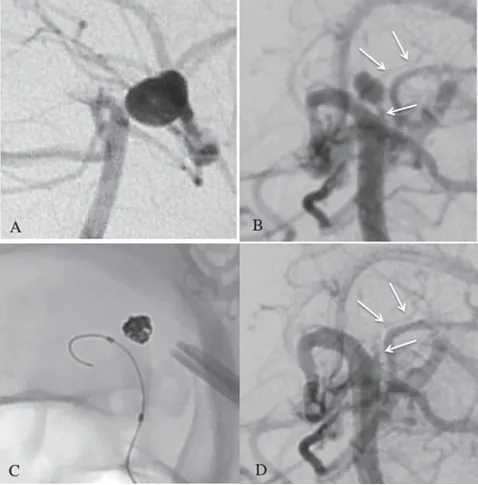

后续数字减影血管造影(DSA)检查发现:新动脉瘤起源于已闭塞左侧P1段上部的穿通动脉(细小血管分支)。左侧P1远端仍处于闭塞状态,确诊为新发穿支动脉瘤破裂。治疗面临双重挑战:

影像学辅助:

(A)既往DSA显示左侧PCA未通,无BA尖端动脉瘤;

(B)右侧椎体血管造影显示丘脑后穿通动脉(pTPA)动脉瘤,pTPA(白色箭头)起源于闭塞左侧P1孔;

(C&D)弹簧圈栓塞后实现完全闭塞,术后检测到丘脑后方穿通动脉(白色箭头)。